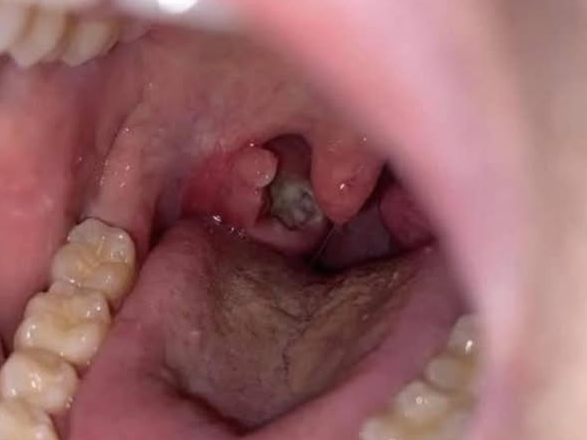

Kamienie migdałkowe to małe, blade lub białe grudki, które mogą pojawić się w tylnej części gardła, często osadzone w migdałkach.

Na pierwszy rzut oka mogą wyglądać jak pryszcze lub nietypowe narośle, co może być niepokojące.

Kamienie migdałkowe, w medycynie znane jako tonsillolithy , to stwardniałe złogi zbudowane z resztek pokarmu, martwych komórek, śluzu i bakterii. Materiały te mogą gromadzić się w maleńkich szczelinach migdałków, zwanych kryptami migdałkowymi. Z czasem ulegają one wapnieniu i tworzą małe kamienie.

• Widoczne białe lub żółtawe grudki na migdałkach

Wiele kamieni migdałkowych można zobaczyć podczas prostego badania gardła. Jeśli kamienie są głębokie lub objawy są poważne, lekarz może zastosować badania obrazowe lub specjalistyczne narzędzia w celu potwierdzenia diagnozy.